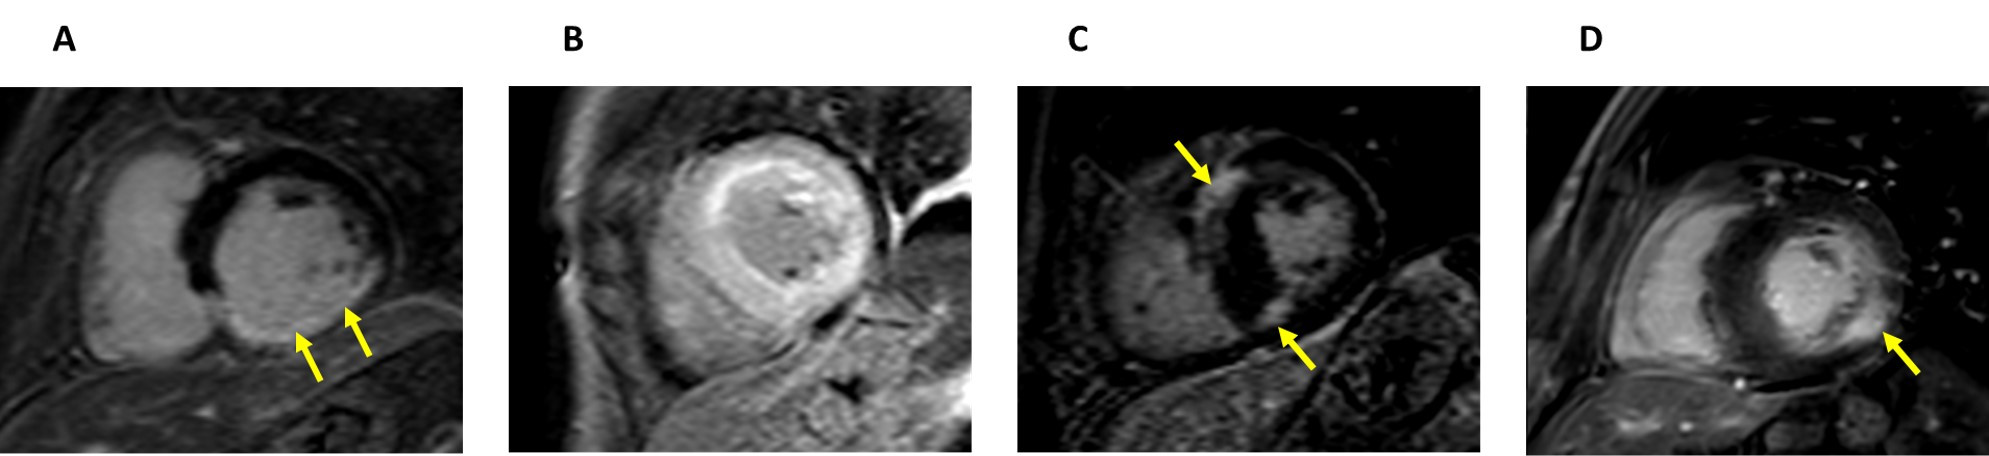

Fig. 5.Different patterns of late gadolinium enhancement in CMR images of diseases that cause left ventricular hypertrophy. (A) Short-axis late gadolinium enhancement (LGE) CMR image of a patient that suffered an inferior myocardial infarction that shows transmural LGE in the inferior wall (arrows). (B) Short-axis LGE CMR image of a patient with amyloidosis, demonstrating a diffuse circumferential pattern of LGE. (C) Short-axis LGE CMR image of a patient with hypertrophic cardiomyopathy and LGE at the junctions of the ventricular septum and right ventricle (arrows). (D) Short-axis LGE CMR image of a patient with FD. Note the enhancement in the inferolateral region (arrow).